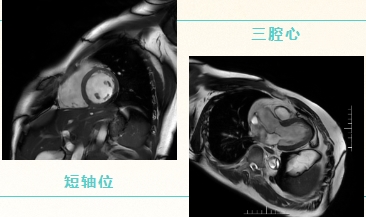

心脏磁共振(Cardiac Magnetic Resonance,CMR)具有多参数、多序列成像特点,可同时对心脏的解剖结构、运动功能、心肌血流灌注、组织成分等进行“一站式”评估,在心衰、缺血性心肌病、非缺血性心肌病以及心脏瓣膜病、心包占位等疾病的诊断中具有重要价值。

相较于其他影像学检查,CMR具有无创、软组织对比度高、无电离辐射等优点。目前,心脏磁共振已成为无创评估心脏结构和功能的金标准。主要通过电影序列,黑血序列,灌注序列以及延迟强化序列对心脏进行综合成像。